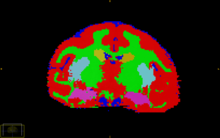

At the 2008 NA-MIC Summer Project Week we optimized EMSegmenter in slicer2 for segmentation of tissue classes and subcortical structures (above image). We have since moved to using the EMSegmenter module in Slicer3. Comparisons between the resulting segmentations show only small differences.